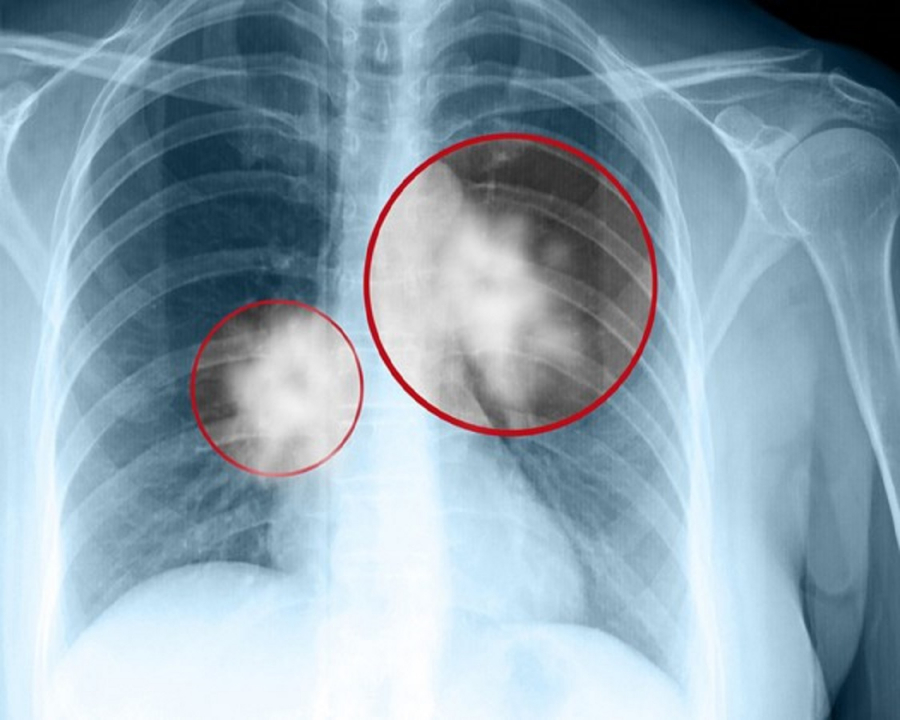

Ung thư phổi là một trong những căn bệnh cướp đi sinh mạng nhanh nhất. Thế nên khi bị chẩn đoán ung thư phổi th́ kể như bị tuyên án tử h́nh. Thế nhưng, nếu biết được vị thuốc quư này bạn sẽ chẳng cần phải lo lắng.

Đây là hai triệu chứng thường gặp nhất ở các loại ung thư phổi. Nguyên nhân do khối u cản trở không khí khiến phổi gặp khó khăn khi hoạt động, máu không được cung cấp đủ oxy, gây ra tức ngực, khó thở.